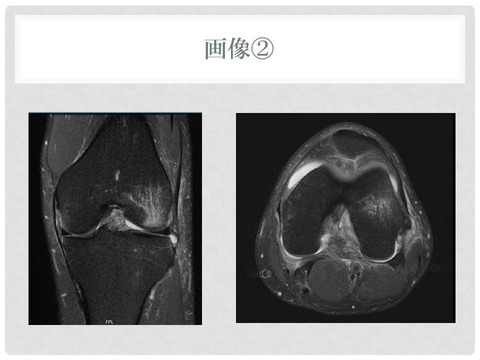

医療機関によるレントゲンなどの画像診断は済んでいます

スライド5